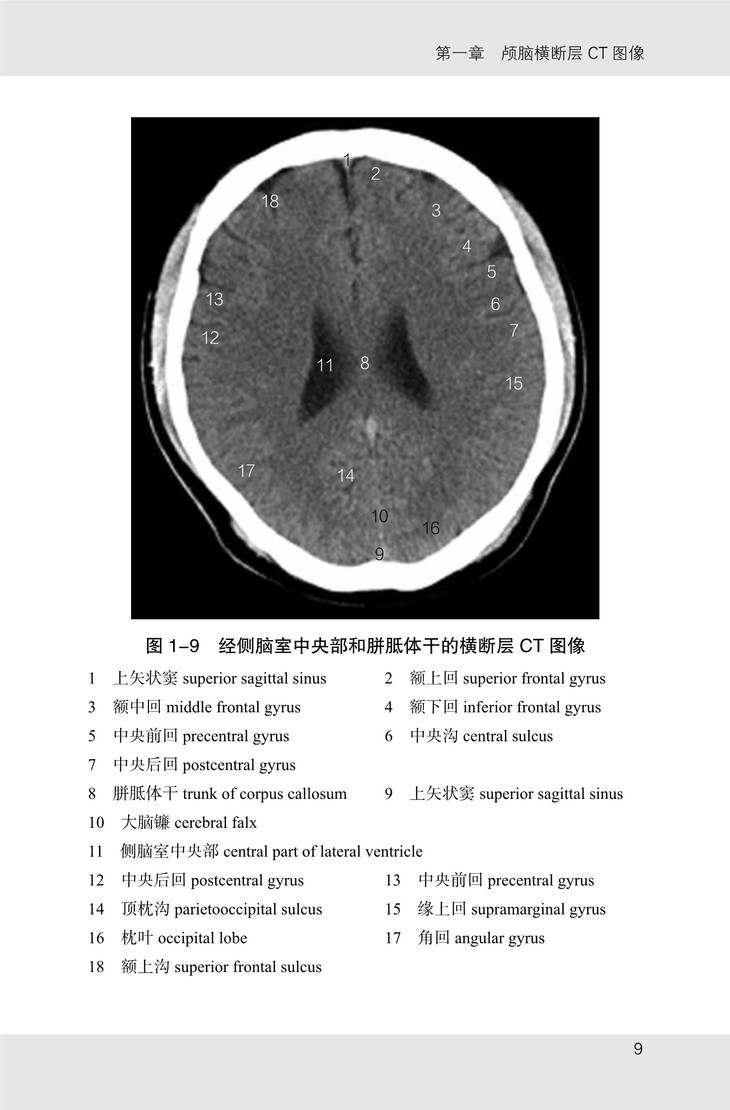

《颅脑影像解剖图谱》共有图像 175 幅,包括以下四个部分:

(1)颅脑 CT 图像,从颅顶至枕骨大孔共有横断层图像 21 幅,扫描基线为眦耳线;